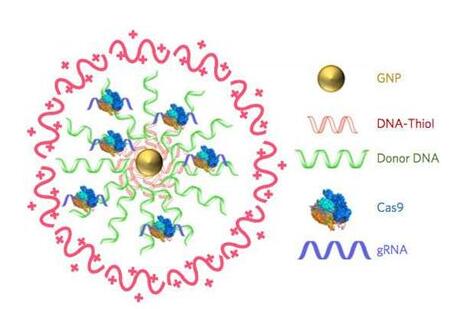

ж–°йҖ”еҫ„иҰҒйўҶ(NAMS)гҖҗAIй©ұеҠЁ+дҪ“еӨ–жЁЎеӯҗгҖ‘

AI+иҚҜзү©еҸ‘жҳҺ